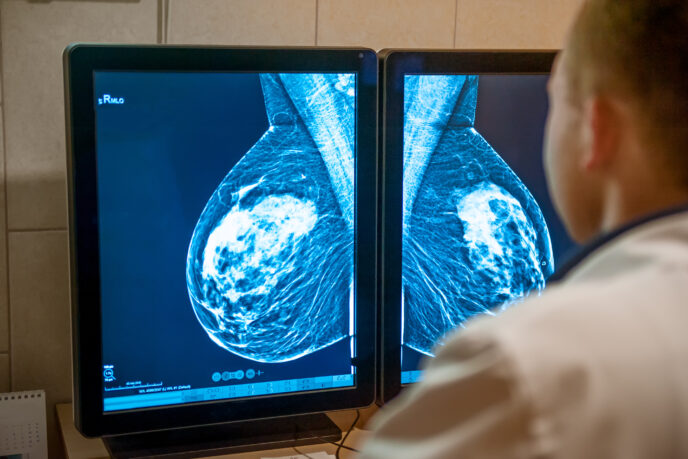

Mehr erfahren zu: "Metastasierter Brustkrebs: Computergestütztes Tool zur Vorhersage von Immuntherapie-Ergebnissen entwickelt" Metastasierter Brustkrebs: Computergestütztes Tool zur Vorhersage von Immuntherapie-Ergebnissen entwickelt US-Forscher haben mithilfe von Computern eine Methode entwickelt, um zu beurteilen, welche Patienten mit metastasierendem triple-negativem Brustkrebs von einer Immuntherapie profitieren könnten.

Mehr erfahren zu: "Triple-negativer Brustkrebs: Neoantigen-DNA-Impfstoff beugt offenbar Rezidiven vor" Triple-negativer Brustkrebs: Neoantigen-DNA-Impfstoff beugt offenbar Rezidiven vor Eine kleine klinische Studie zeigt vielversprechende Ergebnisse für Patientinnen* mit triple-negativem Brustkrebs, die einen experimentellen Impfstoff zur Verhinderung von Rezidiven erhalten haben.

Mehr erfahren zu: "LMU: Analyse von Brustkrebsmetastasen vergleicht verschiedene Methoden" LMU: Analyse von Brustkrebsmetastasen vergleicht verschiedene Methoden Ein internationales Team hat in einer Studie verschiedene Methoden eingesetzt, um die Vielfalt der metastatischen Brustkrebszellen und ihrer Interaktion mit der Umgebung zu analysieren.

Mehr erfahren zu: "Brustkrebs: Neue Therapieoption bei HER2-low" Brustkrebs: Neue Therapieoption bei HER2-low Prof. Annette Lebeau von der Deutschen Gesellschaft für Pathologie informiert anlässlich des internationalen Brustkrebsmonats Oktober über die neuen Therapieoptionen für Krebspatientinnen mit dem Status HER2-low.